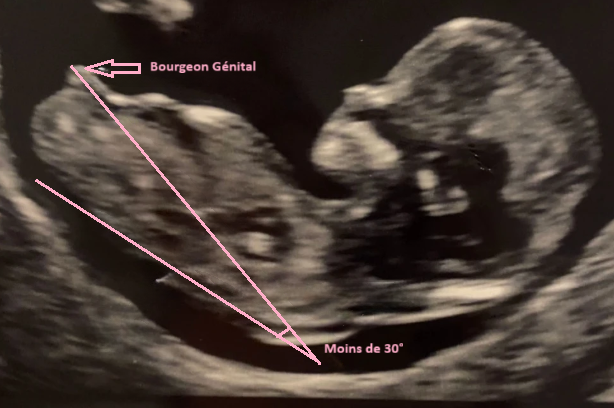

Pour une future fille 💖

Le bourgeon reste plus horizontal, presque parallèle à la colonne (angle < 30°). Il apparaît plus plat et moins proéminent.